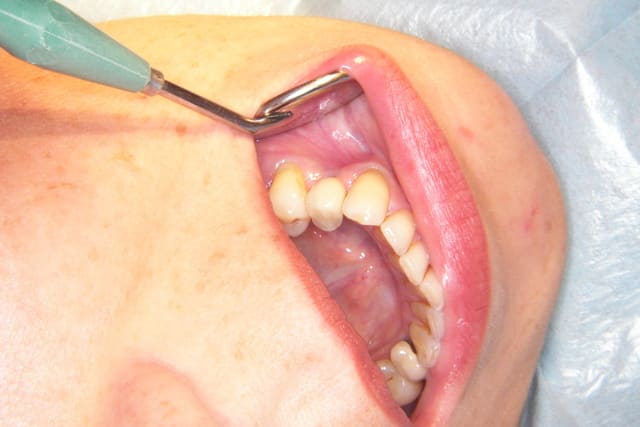

voici les photos en occlusion

avis d’occlusodontistes

à suivre

Le problème c'est l'asymétrie induite (ou conservée) par les extractions, c'est ça ?

absolument, il y a 3 ans c'était un cas qu'on pouvait traiter sans induire d'asymétrie, à condition de ne pas faire d'extraction.

maintenant c'est un cas difficile, car on ne pourra pas récupérer tout l'espace perdu